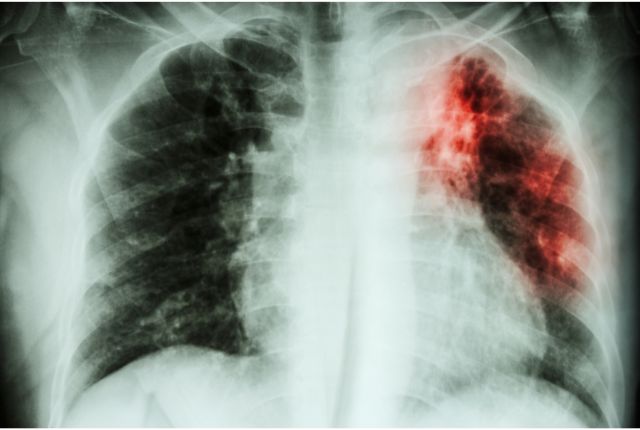

Une radiographie pulmonaire qui révèle des taches irrégulières dans les poumons, caractéristiques de la tuberculose active.

Dépistage de la tuberculose